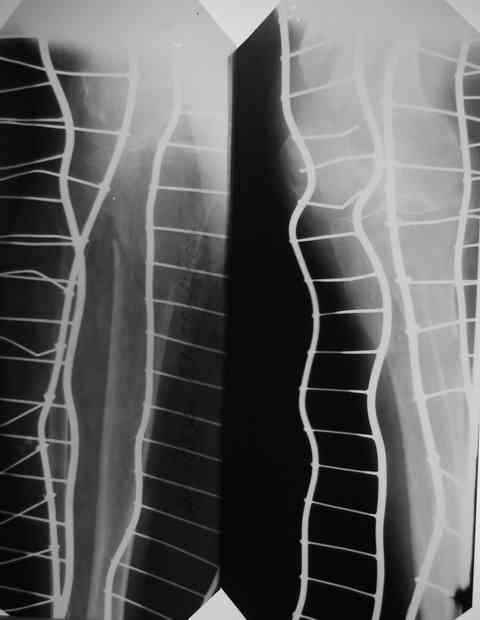

Первый перелом в июне 2002 года - перелом шейки бедра. Лечение консервативно, на данный момент имеем такую картину(см. R-gr.) Падение на бедро в июне 2006 года - не диагностирован второй косой перелом бедра на этой же стороне (просто сказали - полежать) И вот больной с переломом в/3 костей голени (опять же на этой стороне) попадает к нам в отделение. На момент поступления в н/3 бедра истинный ложный сустав. Решили первым этапом зафиксировать бедро с голенью АВФ с дистракцией на бедре (восстановить длину бедра), одновременно для жесткости пришлось зафиксировать колено. Ч/з месяц колено распустили, начали его разработку. На данный момент думаем довести голень на аппарате (или может -ЭКСПЕРТ???), а бедро после устранения всех видов смещения заштифтовать стержнем с блокированием для низких или мыщелковых переломов. НО смущает выраженный остеопороз - удержат ли запирающие винты отломки бедра! С Уважением Владимир Бахарев.